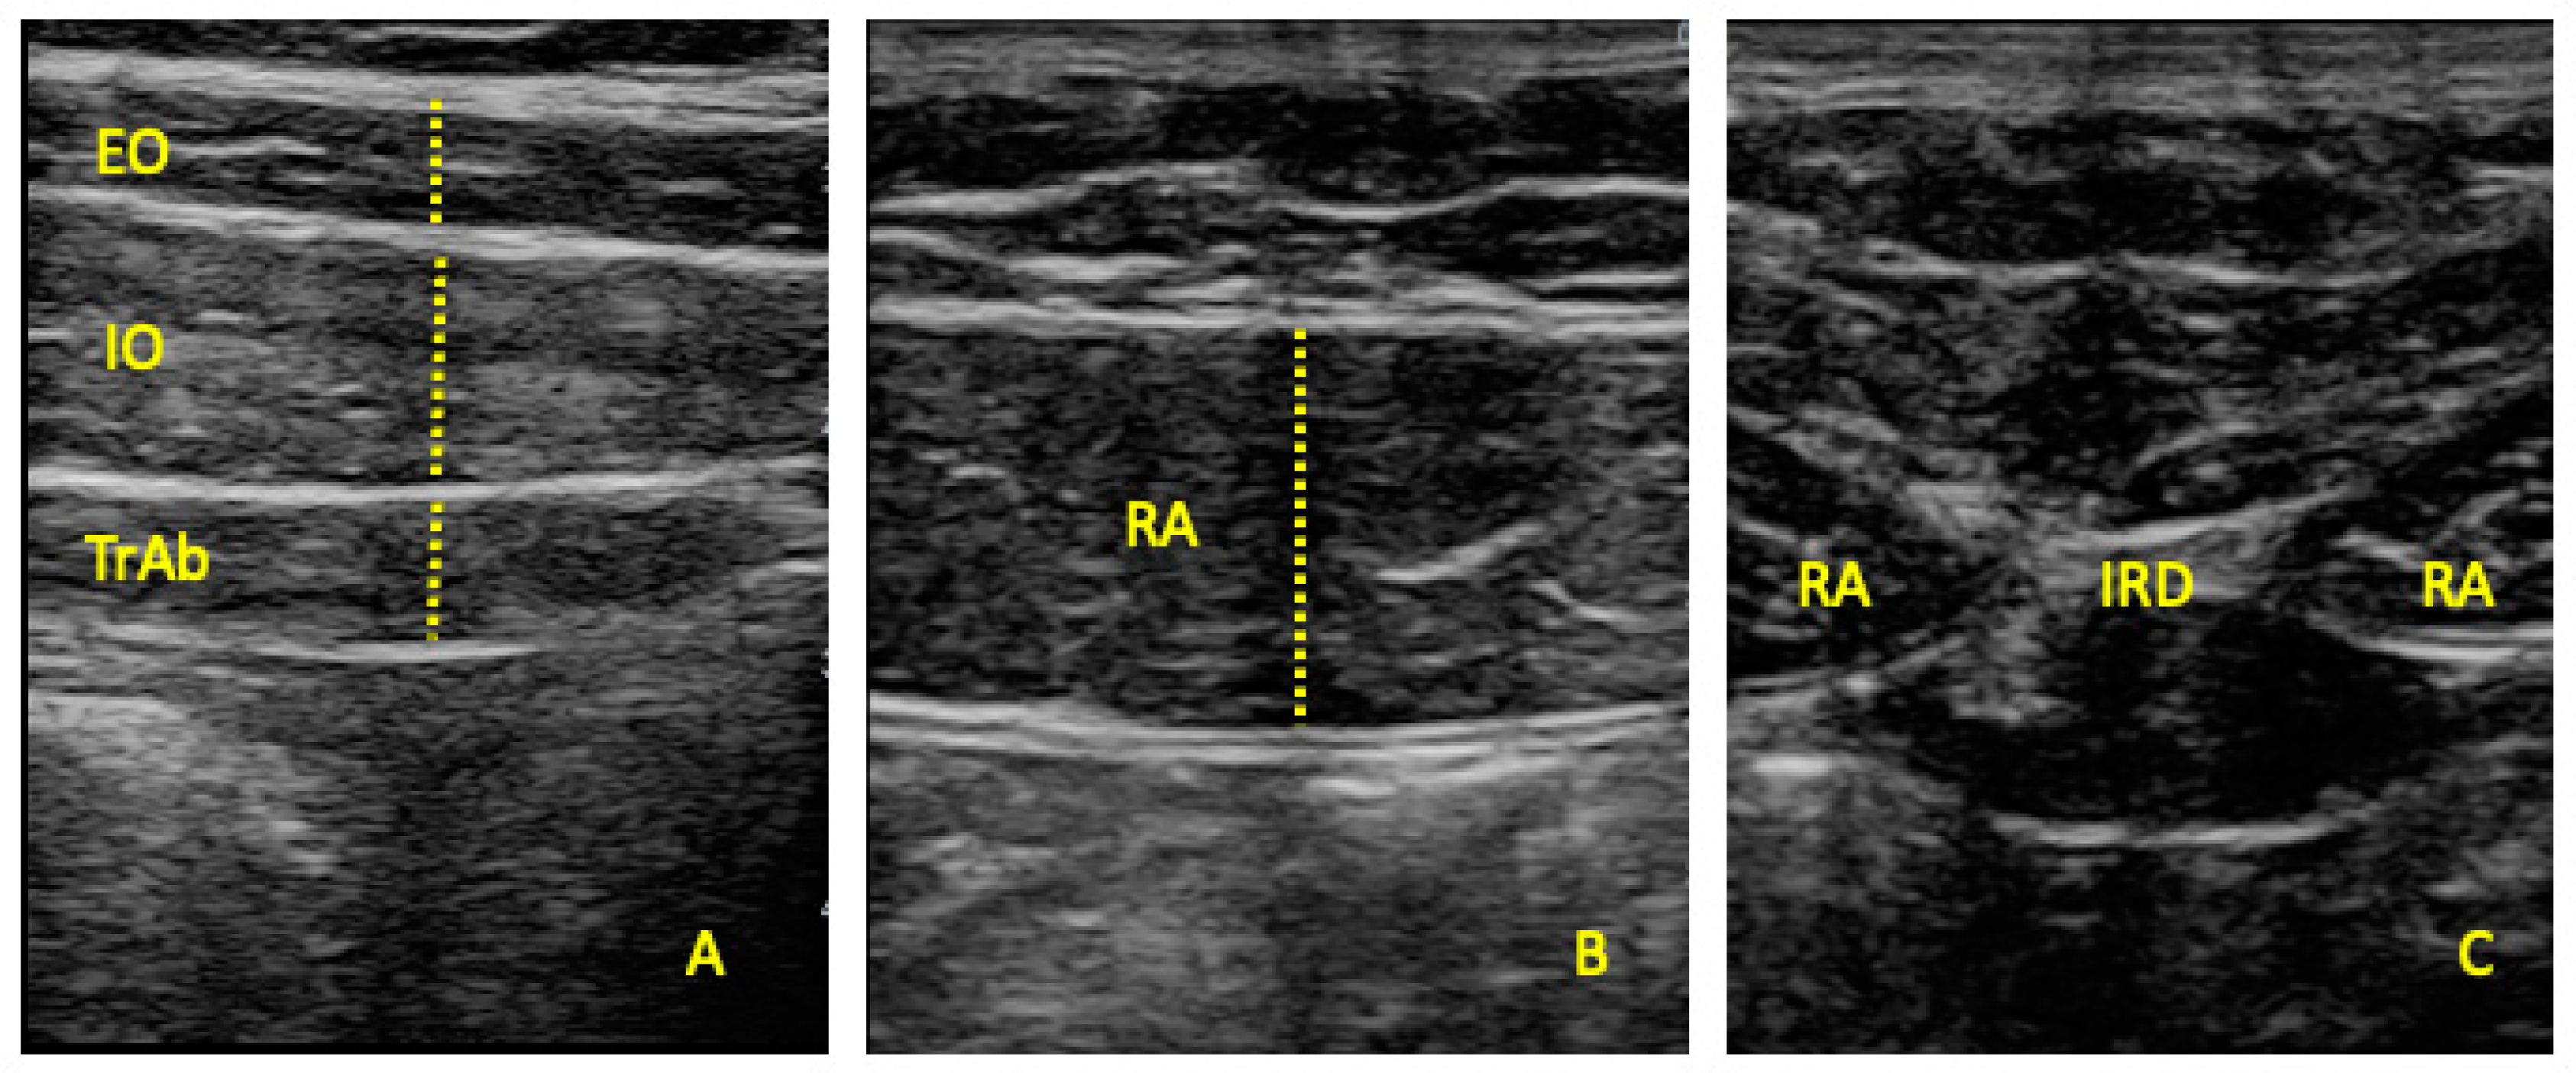

2.4. Outcome Measurements